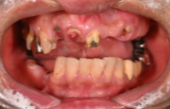

インプラントの症例紹介①

Before

After

主訴

歯が抜けてしまった

治療内容

上顎に対するインプラント治療を行った。

治療費

2,046,000円(税込)

治療期間

1か月

通院回数

3回

※治療回数は1回

想定されたリスク

※最終的な歯が入るまでは仮歯の装着が必要でした。

One Dayインプラントは、手術当日(※術前の検査、術後の経過観察が必要になる場合があります)に仮歯が入るため、その日からしっかり噛めます。入れ歯の必要がなく、治療中の煩わしさを軽減できます。